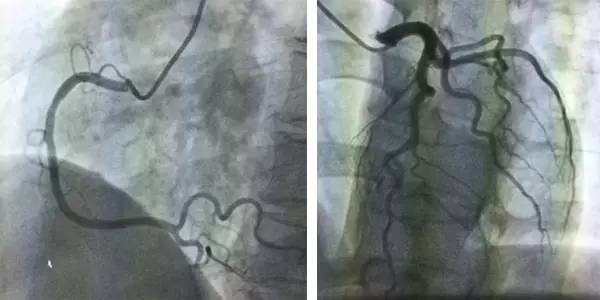

冠脉造影

入院第5天进一步行冠脉造影检查,提示冠状动脉未见明显异常(图3)。

图3